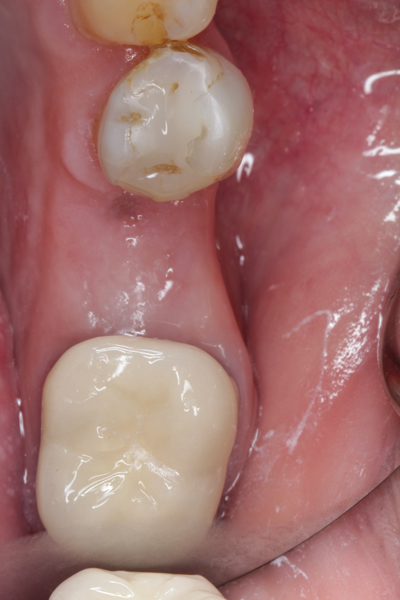

Fig 20. (Case 4) Radiograph of tooth No. 30, which had a hopeless prognosis.

Figure 20

Fig 21. Radiograph of extraction socket. Buccal plate was two-thirds resorbed.

Figure 21

Fig 22. Bone graft was placed in the socket and a d-PTFE barrier was used to cover the graft. The bone graft material was placed beyond the alveolar housing to accommodate shrinkage of graft material and to facilitate attaining a wide alveolar ridge. The barrier was removed after 5 weeks.

Figure 22

Fig 23. Implant inserted in a regenerated ridge after 6 months healing.

Figure 23